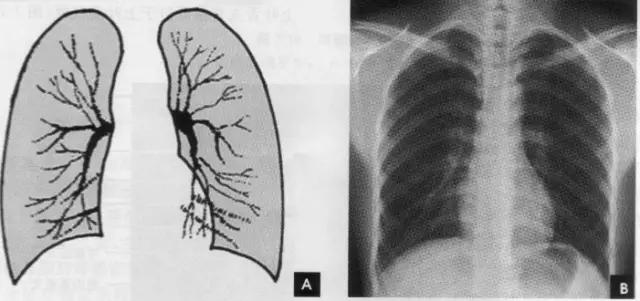

(七)肺纹理 肺纹理为自肺门向肺野呈放射状分布的树枝状阴影,它主要是肺动脉的投影,肺静脉、支气管和淋巴管也参与形成。平片可显示肺纹理的多少,粗细.分布,有无扭曲、变形与移位等。肺纹理由肺门向外围延伸,逐渐变细,至肺野外带渐细小而稀少,距侧胸壁内缘约1cm范围内的肺野基本无肺纹理可见(图下图)。

(六)肺门 x线肺门指肺动脉、肺叶动脉、肺段动脉、伴行支气管以及肺静脉构成。

1、正位肺门影后前位胸片上,肺门位于两肺中野内带第2~4前肋间处,通常左侧肺门比右侧高1~2cm,两肺门的大小和密度大致相等。

2、侧位肺门 侧位胸片上,两饲肺门阴影大部分重叠,若以侧位气管轴线为界,右肺门略信其前下,左肺门大部分在其后上。侧位肺门影前缘为右上肺静脉干形成的椭圆形阴影,前后径为2cm左右;中间纵行透亮区为气管及气管分叉,其内圆形透亮影表示支气管开口,右侧在上,左侧居下;后上缘为左肺动脉弓,下缘由两下肺动脉构成下行的树枝状影。因此,侧位肺门影似一尾巴拖长的“逗号”(如上右图):